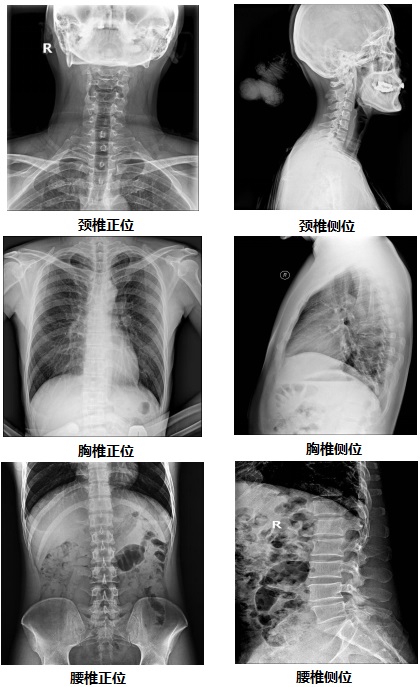

【双板悬吊式dr机PLD7700D部分临床效果图】